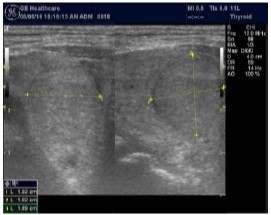

In our study many patients were found to have nodules look very much like PT adenoma, Figure 7 below. At least, 4 patients were subsequently confirmed to have parathyroid adenomas, Figure 8 and 2 patients underwent surgery

Despite the fact that nodular pathology was found to be very prevalent among our study population, it has been found difficult to differentiate between thyroid and parathyroid pathology using ultrasound alone. However, some characteristics of the parathyroid glands might suggest parathyroid pathology in the context of the clinical picture of secondary or tertiary hyperparathyroidism which is very prevalent in ESKD patients’ populations.

Figure 7.Thyroid nodule suspicious for Parathyroid adenoma due to its location

Figure 8.Nodule that proven to be a parathyroid adenoma, volume =5265 mm3

There are 4 parathyroid glands (2 superior, 2 inferior) imbedded within the thyroid gland. The parathyroid glands are bean-like shape and small (20-40 mg) 25. Sonographically, the parathyroid glands have the following features 25:

Hyperplastic glands: hypoechoic, volume <500 mm3.

Nodular glands: hypoechoic. Volume >500 mm3

Histologically, if the excised gland has volume <500 mm3 it is said to be hyperplastic and if the volume is more than 500 mm3 it is nodular hyperplasia in 80% of cases26. In secondary HPT, the increase in the volume of parathyroid glands is associated with increase in vascularity, as evident in Color Doppler imaging 27.